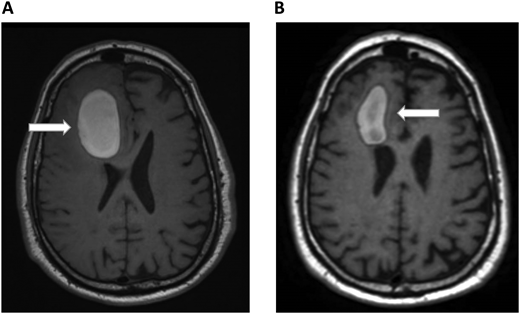

A 61-year-old woman with no prior medical history presented with dizziness and nausea. She was diagnosed with stage IV non–small cell lung cancer (epidermal growth factor receptor exon 17 deletion) with brain metastases and no evidence of ICH (Figure 1). Osimertinib was initiated as first-line therapy. One week after starting osimertinib, she developed right leg edema. Bilateral lower-extremity venous Doppler confirmed a new right calf DVT. Platelets, renal and hepatic function, partial thromboplastin time, and prothrombin time were normal.

Brain MRI in a patient with non–small cell lung cancer and brain metastases. An axial section of a T1 image with contrast shows right frontal metastases (Panel A) and brain stem metastases (Panel B). The white arrows denote these findings.

Hematology was consulted to evaluate whether therapeutic- dose anticoagulation can be given in a patient with newly diagnosed brain metastases. Since her previous brain imaging was 3 weeks earlier, a repeat brain noncontrast CT scan was performed, showing a mild decrease in the size of the brain metastases with no evidence of active bleeding. Her distal DVT was considered to carry a low-intermediate thrombotic risk, potentially enabling reduced-dose anticoagulation if needed. On the other hand, the patient was assessed to have a standard ICH risk, meaning that anticoagulation would likely not lead to a clinically meaningful increase in ICH risk in this setting. Therefore, therapeutic-dose anticoagulation was started with apixaban at 10 mg twice daily for 1 week, followed by 5 mg twice daily. She also continued her anticancer therapy. In this case we did not recommend a routine surveillance brain computed tomography (CT) to assess for ICH after starting anticoagulation.